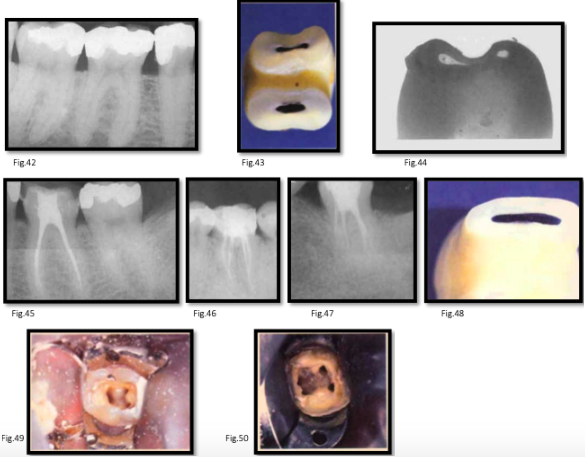

canal anatomy of mn 1st molar

roots: usually 2 (mesial and distal)

mesial root:

2 canals in 87% [fig. 42]

about half merge at apical foramen

canals curve mesially then gradually distal

mesiobuccal canal more curved than mesiolingual

canals may communicate along their length [fig. 43]

grooves on midline wall increase perforation risk [fig. 44]

distal root:

canal centrally located, slightly behind middle bucco-lingual fissure [fig. 45-47]

single canal cases: Broad bucco-lingually [fig. 48]

canal openings:

mesiobuccal → beneath mesiobuccal cusp

mesiolingual → nearer midline